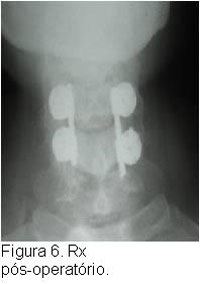

O tratamento do doente vítima de TRM inicia-se na abordagem inicial do paciente politraumatizado, segundo especificações do ATLS , tomando- se os cuidados necessários quanto a imobilização da coluna a fim de se evitar a progressão ou mesmo o surgimento de lesões neurológicas. Após a estabilização do paciente e realização diagnóstica de TRM com exame físico e exames secundários de imagem como Rx, TC ou RM cervical, deve-se proceder a estabilização da lesão cervical, geralmente com o uso de tração em halo craniano, até a programação do tratamento definitivo, que geralmente consiste na redução cruenta da fratura e fixação interna da mesma.Caso o paciente tenha sido atendido nas primeias 8 horas após o trauma deverá ser instituído a corticoterapia, salvo os pacientes com contra-indicações, segundo protocolo instituído pelo NASCISIII, a fim de evitar possíveis lesões secundárias à medula.Este protocolo consiste na aplicação de metilpredinisolona na dose de 30mg/kg ev na primeira hora, seguido de 5,4mg/kg/hora nas próximas 23hs, isto quando paciente chega ao hospital dentro de 3hs do trauma. Quando chega entre 3-8hs, manter esquema de 5,4mg/kg/hora por 48hs. Após 8hs não realizar corticoterapia. Contra-indicações para corticoterapia: gravidez, criança, imunossuprimido, fx exposta, infeccção grave ou risco de vida.Cuidados: monitorar PA, glicemia, e realizar proteção gástrica.

O tratamento cirúrgico tem se beneficiado muito das inovações tecnológicas que propõem cada vez mais técnicas mais rápidas, seguras e com maior poder de estabilização da lesão óssea.O tratamento farmacológico restringe-se a corticoterapia a fim de evitar lesões secundárias, porém novas drogas estão sendo testadas e poderão ser introduzidas num futuro próximo, como o gangliosídeo.O tratamento biológico consiste na maior esperança para o lesado medular, a expectativa de que o uso de células tronco possa proporcionar uma restauração da via neurológica acometida no trauma, vem estimulando diversas pesquisas nesta direção, entretanto ainda estamos em fase inicial desta metodologia.Já a terapia por meios físicos, como a câmara hiperbárica, não demonstrou benefícios nos ensaios animais (figuras 2, 3, 4, 5, 6, 7).